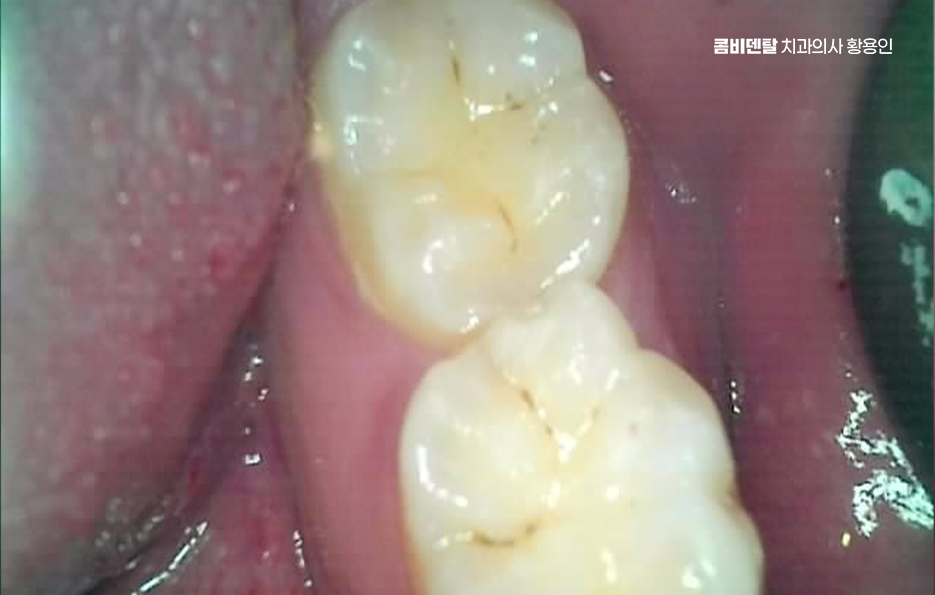

또 하나 중요한 점은, 사랑니를 발치한 후 생긴 공간이 오히려 어금니 충치 치료를 더 수월하게 만들어 준다는 점으로 사랑니가 있을 때는 치료 기구 접근이 힘들었지만, 발치 후에는 시야가 확보되면서 어금니 치료가 더 깔끔하고 정확하게 가능해질 수 있어요

그,래서 사랑니를 먼저 빼고 나서 어금니를 치료하면 예후도 좋아지고, 애초에 사랑니의 영향을 받았던 상태이기 때문에 충치 재발률도 낮아지는 거예요.

결론적으로 말하면, 사랑니 발치 후 충치 치료에 있어서 사랑니와 어금니 충치가 동시에 발생했을 때 치료 순서와 방향을 잘 잡는 게 중요하며 단순히 통증 있는 쪽만 치료하는 게 아니라, 원인과 현재 상태를 정확하게 파악하여 치료 계획을 체계적으로 세워야 하며 특히 어금니 충치를 뒤늦게 통증으로 자각하는 경우에는 신경 손상의 가능성이 높아지기 때문에 꼭 아플 때 치과를 방문하는 것만이 아니라 정기적으로 검진하여 사랑니의 발치 시점 및 평소 치아, 잇몸 건강관리에 있어서도 잘 관리하시길 바라고 있어요